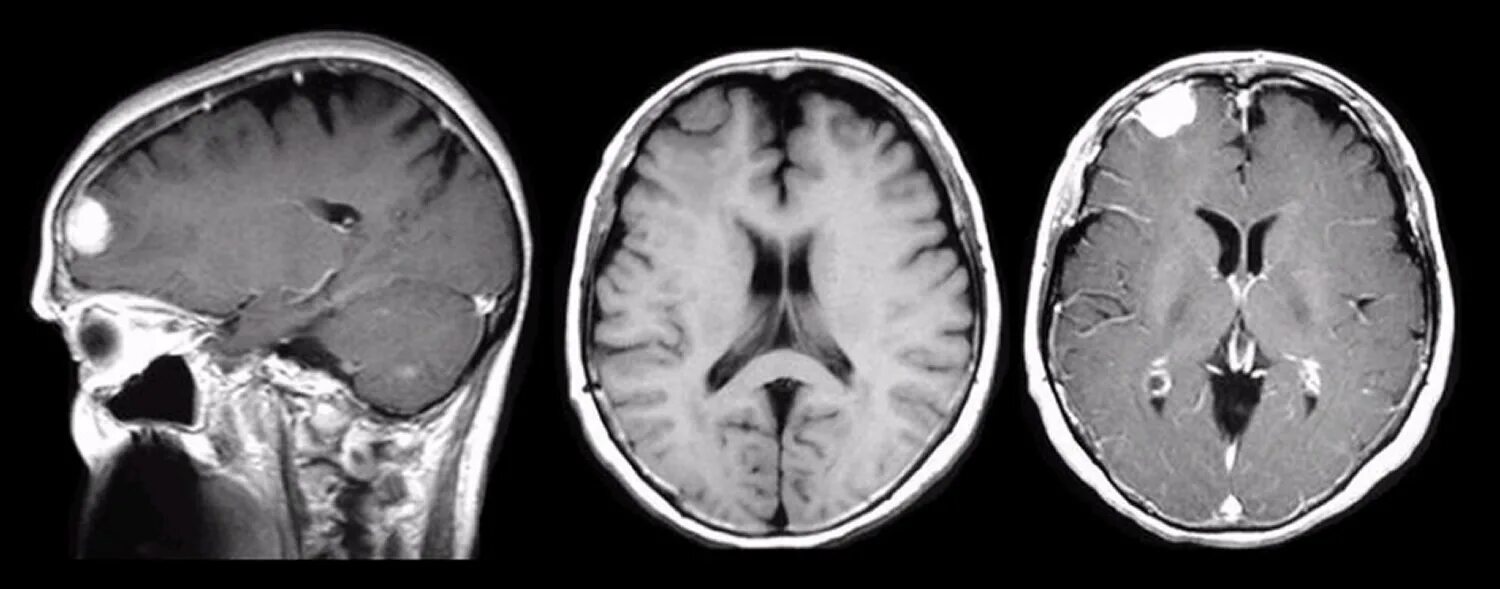

Бластома мозга